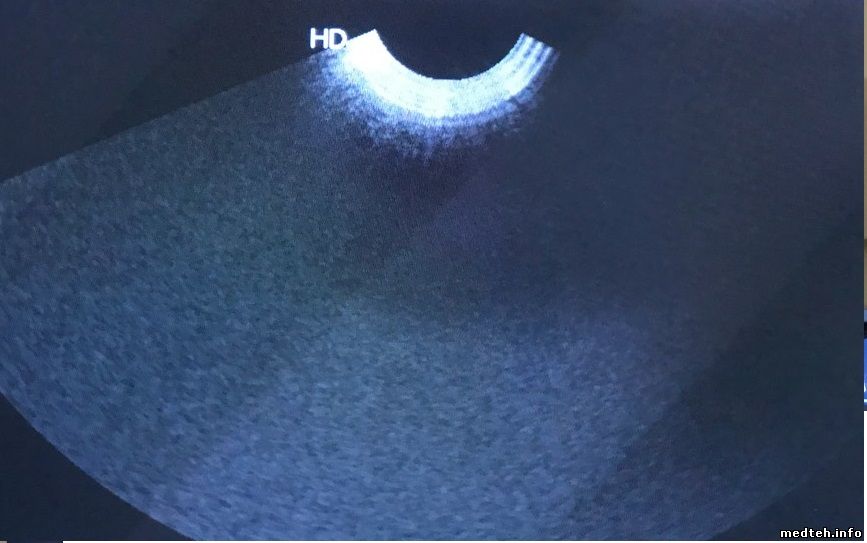

Подскажите, что может быть двоятся и искажаются объекты в определенных секторах датчика вагинального, какие соображения? Прикладываю фото сухого датчика и с дефектом, изображение фантома.

7521158.jpg (29.0 Kb) · 1084120.jpg (53.0 Kb) · 0850773.jpg (37.7 Kb)